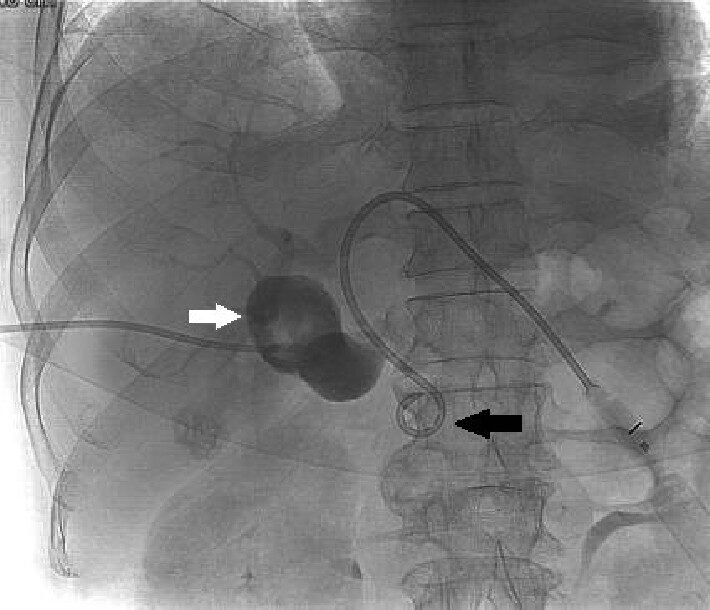

The PTBD in Madurai procedure is performed under real-time ultrasound and fluoroscopy guidance to ensure accuracy and safety. After local anesthesia is given, a fine needle is inserted through the skin into the liver to access the bile duct. Contrast dye is injected to clearly visualize the site and extent of blockage. Once access is confirmed, a drainage catheter is placed to allow bile to drain either externally into a bag or internally into the intestine.